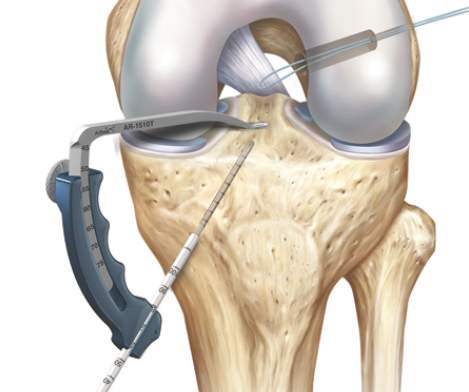

Anlegen des Bohrkanales im Oberschenkel über den mittels Zielinstrument vorgelegten K-Draht*

Anlage des Bohrkanals am Unterschenkel über das Zielinstrument*

Anlage der Bohrkanäle in exakter anatomischer Position. Im femuralen Kanal befindet sich ein Draht durch den der Einzugsfaden eingebracht wird.

Hier wird der tibiale Kanal angelegt. Das Zielinstrument und der Führungsdraht sind gut sichtbar . Im femuralen Kanal ist der Shuttlefaden bereits eingezogen.